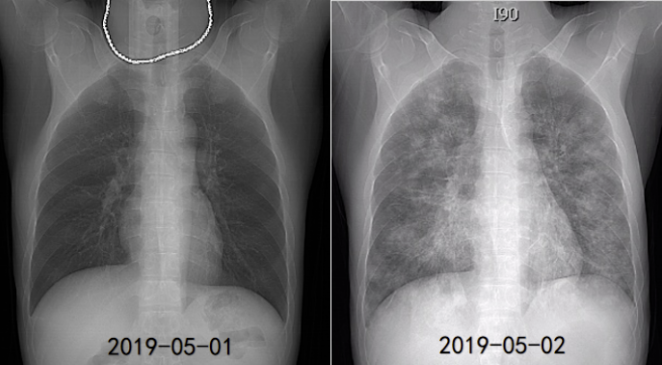

病例1:38岁男性患者,有2型糖尿病基础病史,以"高热、咳嗽4天,呼吸困难1天"为主要表现,呈急性病程。患者病情进展极快,短时间内即出现呼吸衰竭、脓毒性休克等严重并发症。影像学检查显示,2019年5月1日胸部CT未见明显异常,仅1天后(5月2日)复查,胸部CT已出现两肺弥漫性渗出改变。最终病原学检查确诊为耐甲氧西林金黄色葡萄球菌(Methicillin-Resistant Staphylococcus Aureus, MRSA)感染。

图1 病例1胸片变化